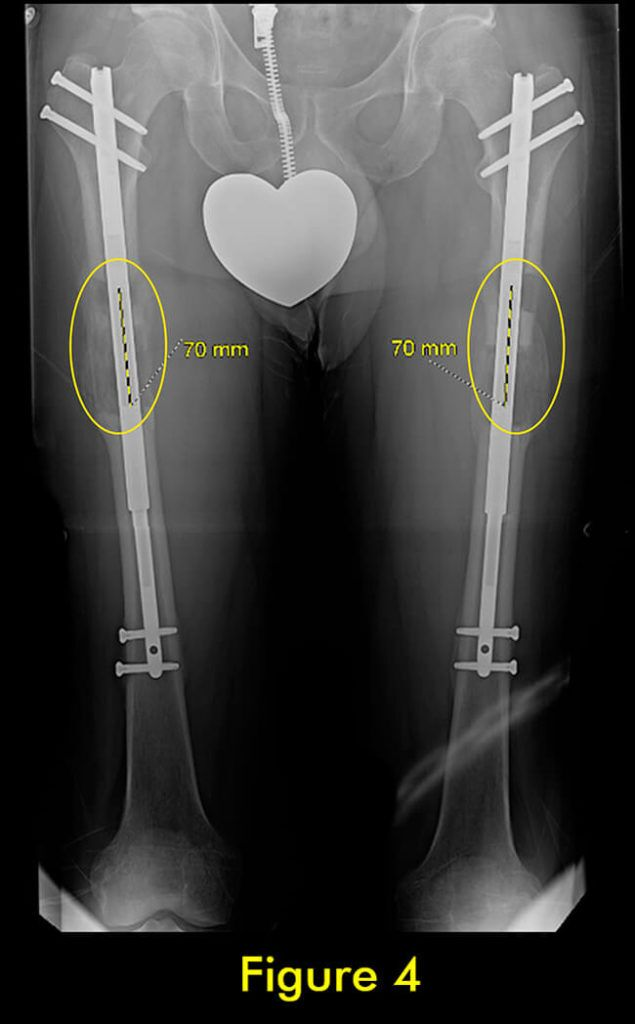

7 腓骨并发症

随着胫骨的延长,腓骨也必须延长。植入式加长装置仅延长和固定胫骨。腓骨必须固定在胫骨上,以便它与胫骨一起拉长。如果腓骨固定不固定或固定不充分,它不会像胫骨那样拉长,并会导致严重的后果,包括脚踝半脱位和关节炎以及膝盖屈曲挛缩。

固定方法至关重要。许多外科医生只将腓骨的下端固定在胫骨上。这会导致腓骨过早巩固,并在其上端从胫骨向下拉和脱臼。固定腓骨两端很重要。大多数外科医生避免这样做,因为这在技术上很难做到。

我们为所有患者的腓骨两端固定。植入式加长时,腓骨必须用螺钉固定在胫骨上;上端有一个螺钉,下端有一个螺钉。螺钉的角度、水平、位置、直径和类型都很重要。一个常见的错误是将螺钉水平放入两块骨头之间。这不足以防止腓骨从脚踝处的胫骨上拉开。这是非常微妙的,即使脚踝腓骨长度的几毫米差异也会给患者带来短期和/或长期后果。切除腓骨的一部分以防止腓骨不分离是另一种应避免的常见方法。它会导致腓骨不愈合,从而导致胫骨以后出现应力性骨折。

此外,它通常不会阻止腓骨从胫骨上拉开。因此,腓骨并发症与植入式延长装置的类型无关,而是与外科医生选择将腓骨固定到胫骨的方法和切割腓骨的方法有关。腓骨愈合的范围可以从过早巩固到完全不愈合。后者通常不需要治疗,只要胫骨牢固愈合。前者需要重复腓骨截骨术。

在外部机构胫骨身材延长并出现双侧并发症的患者。他发展了胫骨和 Abu/a 延迟结合,右侧是敲击 {外翻),左侧是弓形 {内翻),两侧是 f1exion {procurvatum}。我们在手术室使用临时外部斧头机对两侧进行了急性矫正,并放置了新的胫骨杆。我们在 Abu/a 延迟结合上放置了逆行杆。